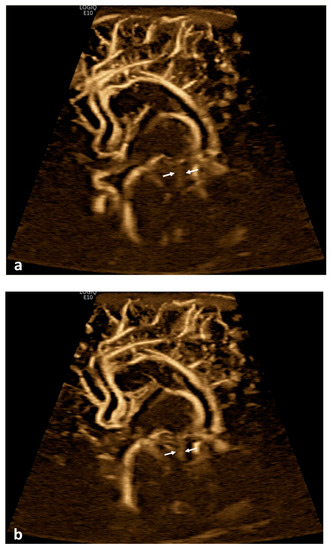

Twenty patients (19.8%) demonstrated apparent CSF flow detectable using MVI in at least one of the ventricular structures: 11 (10.9%) in the third ventricle, 16 (15.8%) in the cerebral aqueduct, and 17 (16.8%) in the fourth ventricle (Figure 1 and Figure 2). Of these 20 patients, 13 had IVH as visualized in grayscale US; flow direction was detected as craniocaudal in 15% (n = 3) of patients, caudocranial in 70% (n = 14), and bidirectional in 15% (n = 3) (Supplemental S1 and S2; Table 1). The IRR for detection of CSF flow was 0.662, p < 0.001.

Figure 1.

Cerebrospinal fluid (CSF) flow visualized in the ventricular system. A 15-day-old term girl with a history of bilateral grade III intraventricular hemorrhage and hydrocephalus underwent brain ultrasound. This patient also had cardiovascular comorbidities, including dextro-transposition of great arteries, ventricular septal defect, and tricuspid regurgitation. (a–c) Sagittal B-Flow demonstrates turbulent caudocranial CSF flow in the cerebral aqueduct (arrows). The entire clip is provided as Supplemental Material S1.